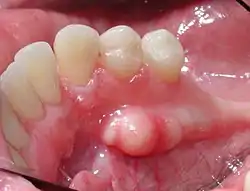

![]() حيد الفك السفلي في منطقة الأسنان قبل الطاحنة. حيد الفك السفلي في منطقة الأسنان قبل الطاحنة. | |

حيد الفك السفلي في منطقة الضواحك